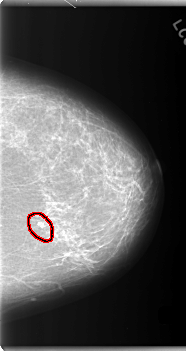

C_0106_1.LEFT_CC

LEFT_CC LINES 5952 PIXELS_PER_LINE 3152 BITS_PER_PIXEL 12 RESOLUTION 50 OVERLAY

FILE: C_0106_1.LEFT_CC.OVERLAY

TOTAL_ABNORMALITIES 1

ABNORMALITY 1

LESION_TYPE CALCIFICATION TYPE PLEOMORPHIC DISTRIBUTION CLUSTERED

ASSESSMENT 5

SUBTLETY 5

PATHOLOGY MALIGNANT

TOTAL_OUTLINES 1

BOUNDARY